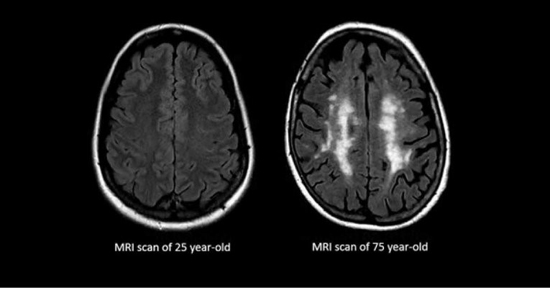

The researchers believe that this is because as we age, the microglia – the class of brain cells responsible for routine cleanup and immune responses – decline and lose their ability to engage in the sort of “maintenance” work that brains require.